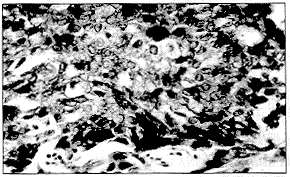

宮頸殘端呈不同程度糜爛,見贅生物呈菜花狀、結節狀、潰瘍或形成空洞,宮旁組織增厚、呈結節狀等。